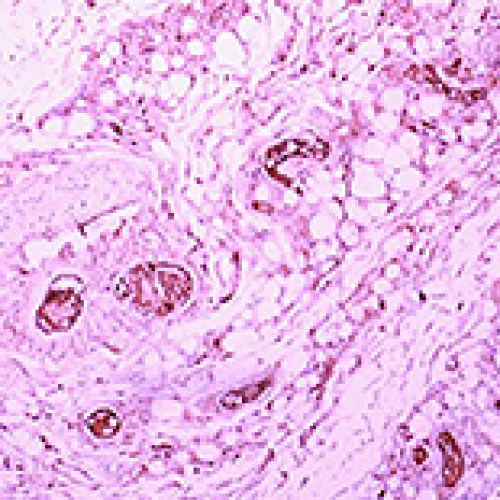

24 Oct 2022 : Animal Research

Effect of Antilogous Platelet-Rich Plasma on the Revascularization of Rabbit Prefabricated Flap

Ke Xie, Meixia Huang, Yan Zheng, Daiqing Chen, Junling Hu, Jiansheng Zheng